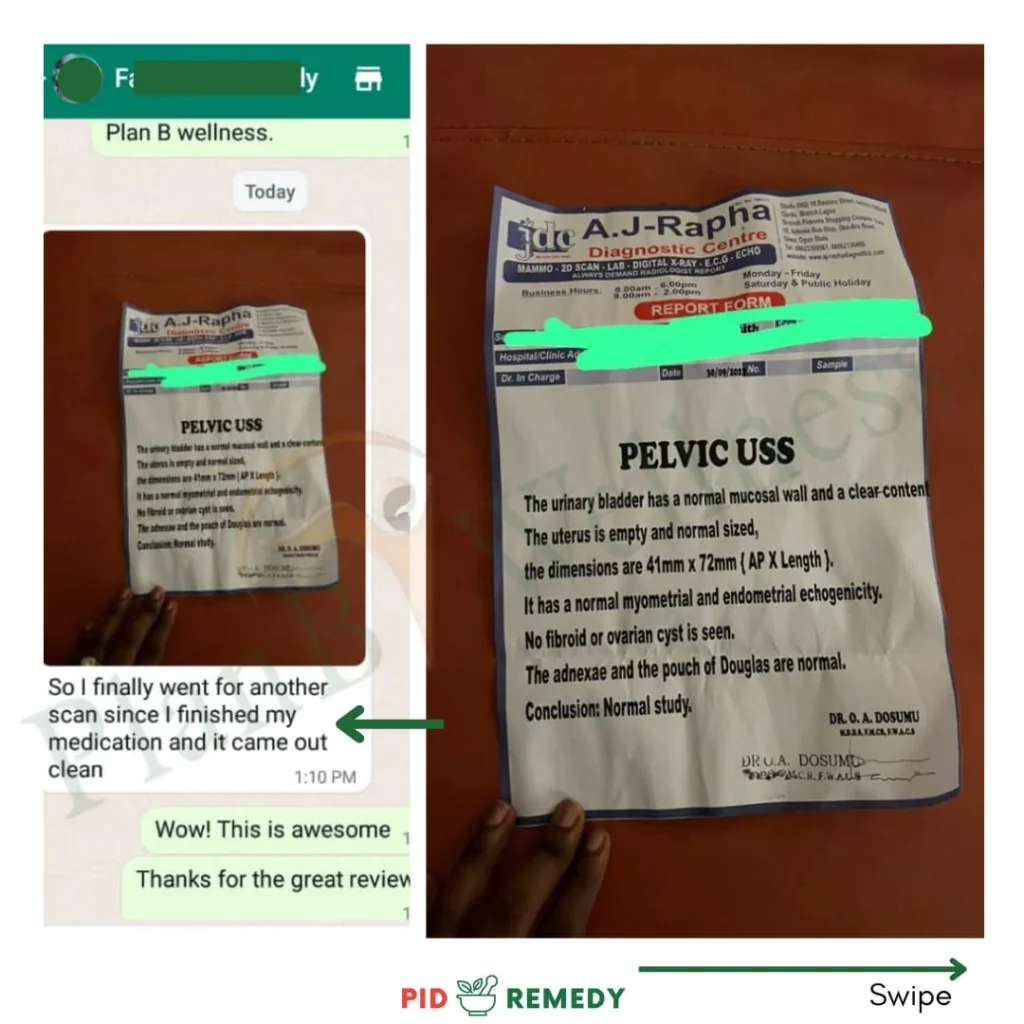

Day 30…

She went for another test.

No growth.

No pus cells.

No infection.

No PID.

A real, solid, God-I’ve-been-waiting-for-this negative result.

Zainab was free from PID.

Completely!

Our Happy Customers Who Love The PID Remedy Kit

Real Reviews From Real People

Our Happy Customers Who Love The PID Remedy Kit

Real Reviews From Real People